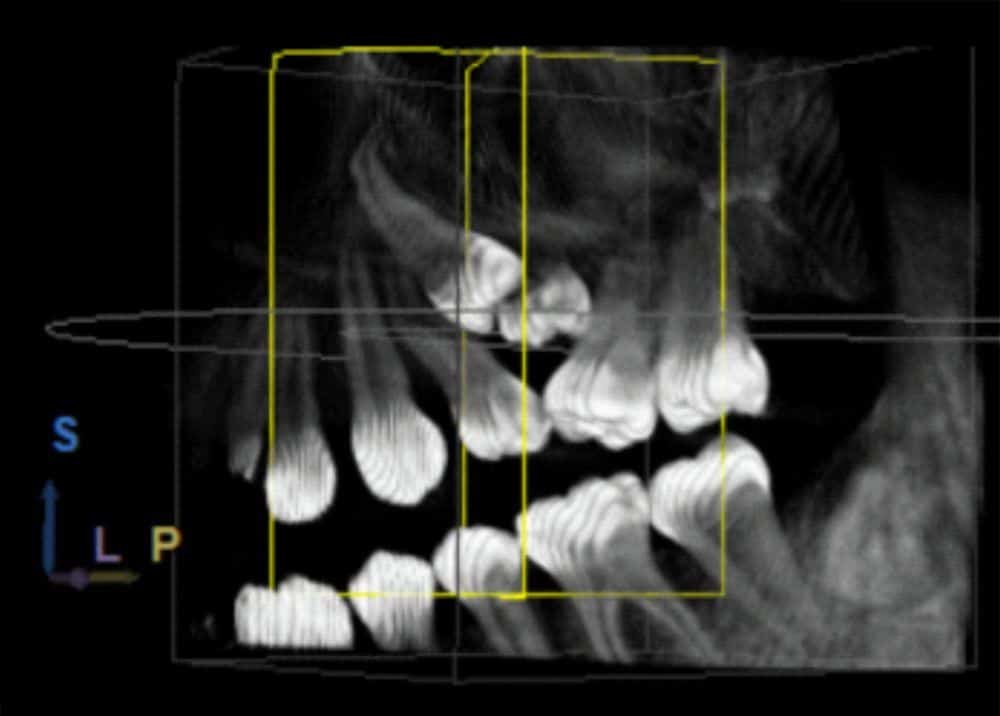

En algunos casos puede ser necesario extraer las llamadas “muelas del juicio” o tercer molar, en otros, puede ser necesaria la extracción de otras piezas tales como premolares o incisivos, lo cual dependerá de las particularidades del caso clínico.

El procedimiento quirúrgico como tal va a depender de la complejidad de la pieza dental en particular, si esta se encuentra sana y correctamente posicionada en boca, el procedimiento será sencillo y corto, sin embargo si la pieza dental se encuentra en una posición anómala y/o cubierta por hueso, la extracción puede complejizarse un poco más pudiendo ser necesaria la utilización de instrumental rotatorio para poder retirar el hueso que cubre al diente y acceder a él.